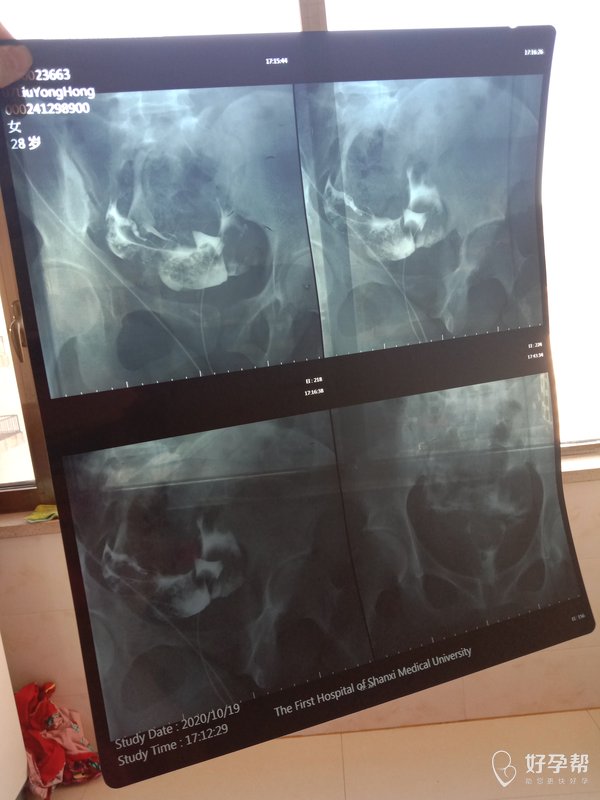

结婚五年一直怀不上检查也做了找不出原因下一步